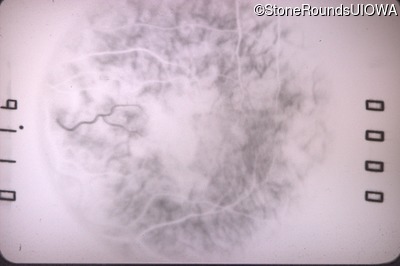

Fluorescein Angiography - Right - 20/50 +2

Exemplar

Fluorescein Angiography - Left - 20/160